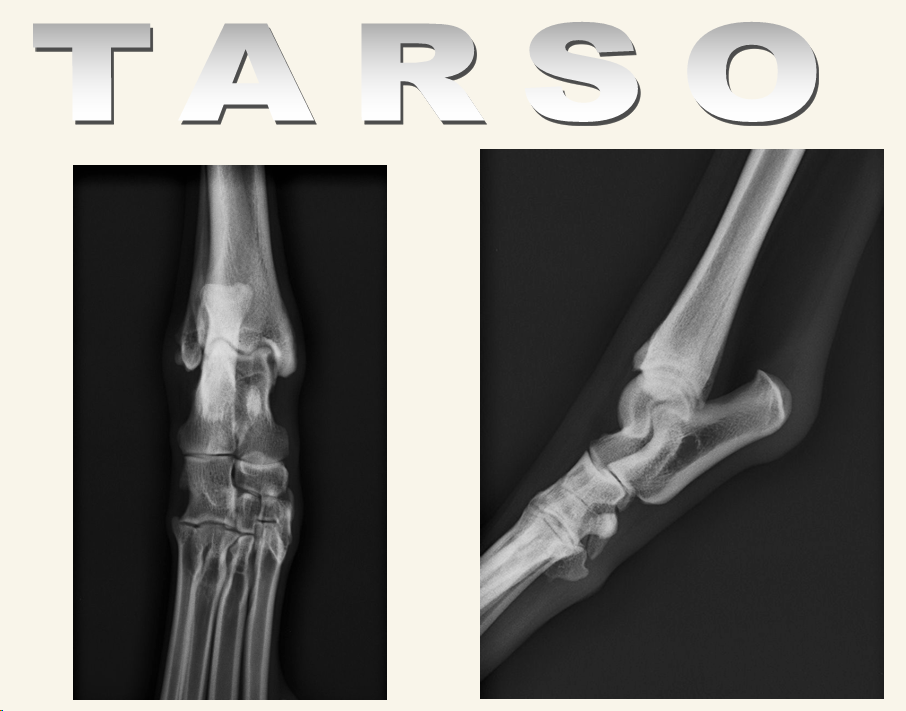

Tarso

Proyecciones ML y CdCr ó CrCd

Posibles problemas:

- Fracturas: Del maleolo, huesos tarsales, o tuberosidad del calcaneo. Se puede romper el calcaneo por estres al ligamento sobre todo, por su rotura por ejemplo. Si es antigua se ve calcificacion, si es antigua, solo inflamación

- Luxaciones

- Subluxacion Intertarsal: Escalon entre huesos centrales del tarso y articulacion con tibia, inflamacion del ligamento

- Subluxacion tarso-metatarsiana: Esta SI produce dolor, inflamacion y cojera.

- Hiperextension, posbles fracturas proximales en metatarso. Radiografia en estres si se sospecha daño al ligamento

- Hiperextension o hiperflexion

- Recordad que cada hueso del tarso articulan, por tanto son susceptibles de tener enfermedades degenerativas musculares o EDA.